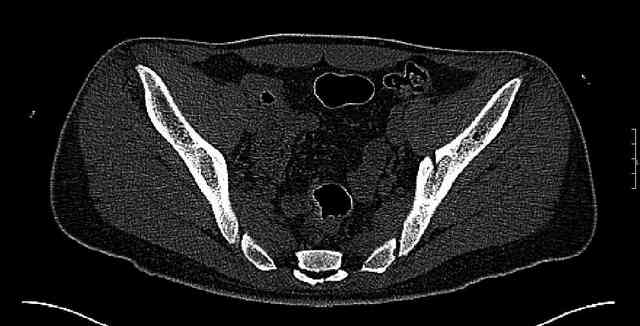

Re: Нелеченный перелом вертлужной впадины

Some more images. Does it help to guess which part of the acetabulum is displaced?